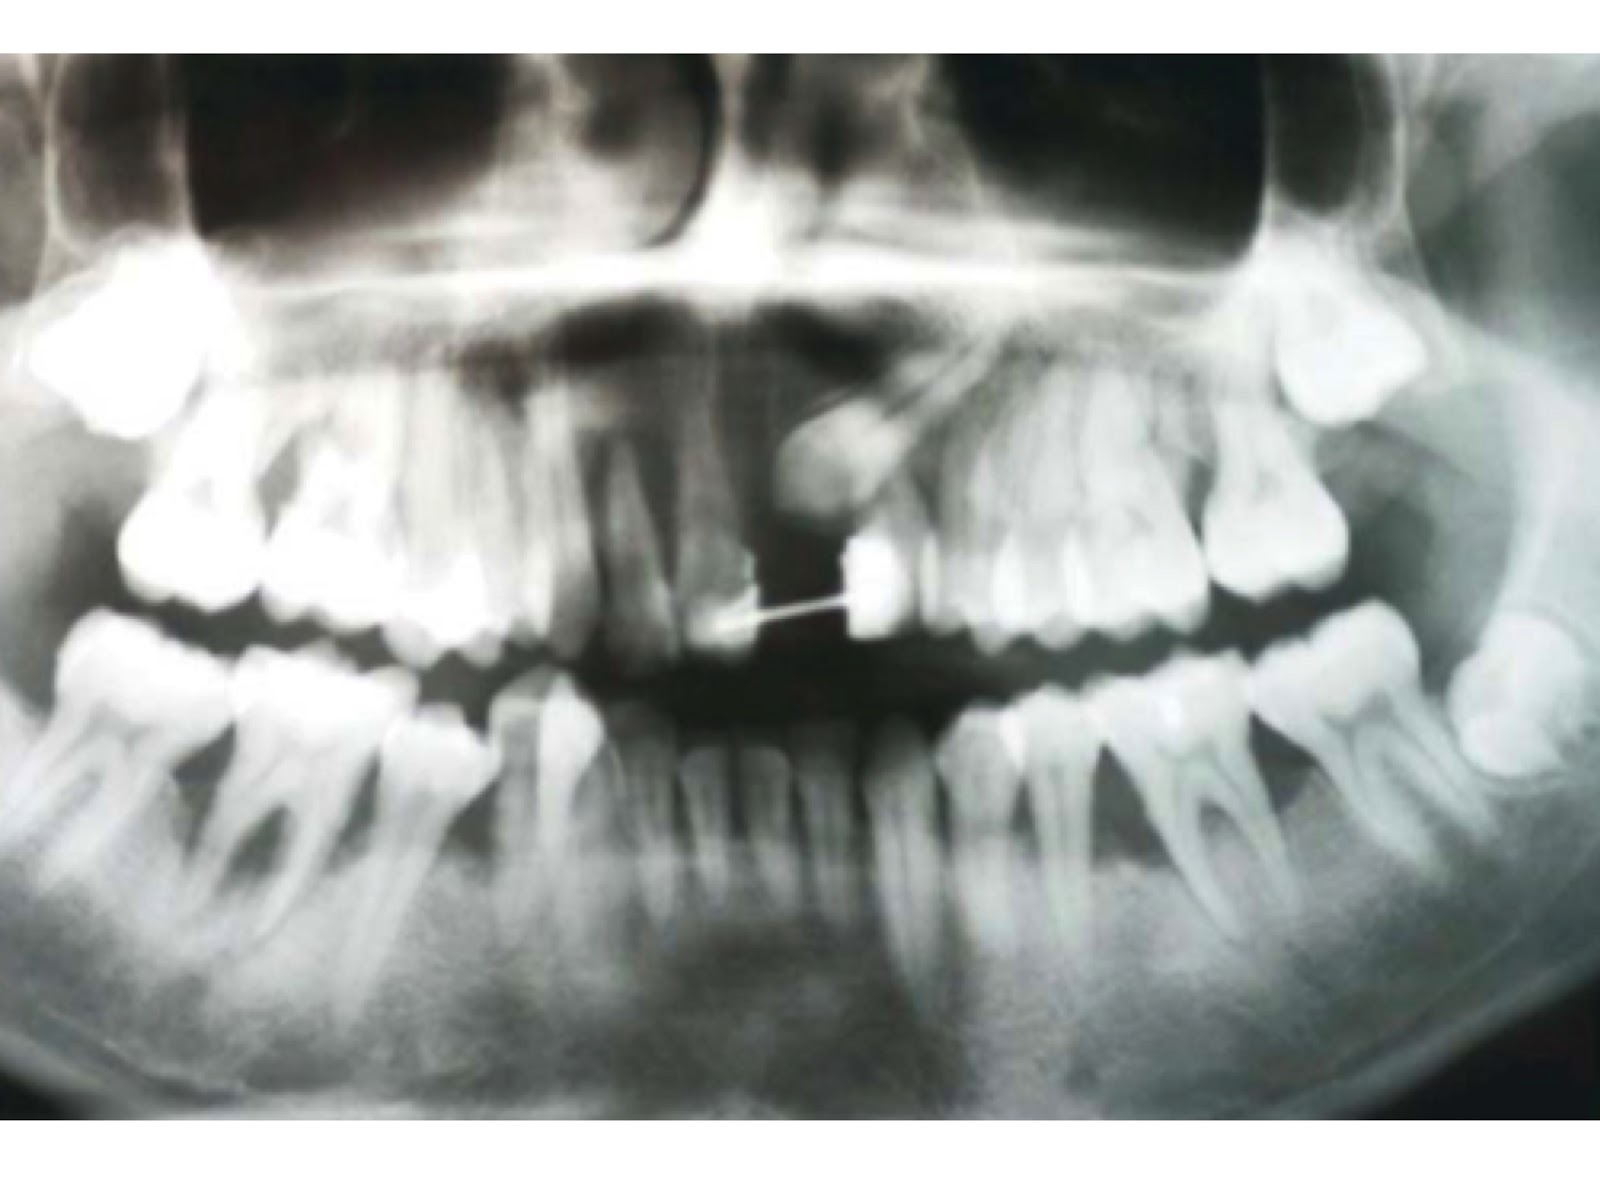

Vamos direto ao ponto sobre como tratar a periodontite agressiva juvenil. O primeiro passo é crucial: um diagnóstico rápido e preciso. Não dá para brincar com isso, sabe? Um dentista experiente vai ser capaz de identificar os sinais logo de cara. Ele vai olhar para as gengivas, verificar a perda óssea e avaliar a velocidade com que isso acontece. Isso é fundamental porque a periodontite agressiva juvenil tem suas particularidades e precisa de uma abordagem específica.

Entender a causa raiz é parte desse diagnóstico. Às vezes, fatores genéticos podem estar envolvidos, e isso a gente não controla. Mas outras vezes, o acúmulo de placa bacteriana e a dificuldade em fazer a higiene correta acabam contribuindo. O dentista vai investigar tudo isso com exames clínicos e, se necessário, radiografias. Ele vai querer saber o histórico familiar, seus hábitos de higiene e se você tem alguma condição de saúde que possa influenciar.

Vamos falar sério agora sobre periodontite agressiva juvenil. Se você ou alguém que você conhece está lidando com isso, sabe que é um assunto delicado. Basicamente, quando a doença periodontal avança e a inflamação já causou perdas ósseas significativas, a cirurgia pode ser o caminho. É aquela situação em que a limpeza profunda que fazemos não consegue mais alcançar as bactérias mais problemáticas.

Eu já vi casos onde a gengiva se retrai muito, deixando a raiz do dente exposta. Isso não é só questão estética, viu? Aumenta a sensibilidade e o risco de cáries nessa área. A cirurgia periodontal entra para tentar recuperar o suporte dos dentes, removendo as bolsas periodontais e, em alguns casos, até regenerando o osso perdido. É um procedimento para quando outras abordagens não foram suficientes, entende?